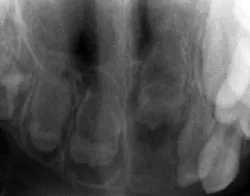

His parents report that Paul had been diagnosed at 10 months with rickets and also perinatal encephalopathy. He also had repeated infections up until the age of three and multiple tooth infections were noted in early life as well (see Figure 1).

His treatment has consisted of some extractions with the placement of a partial denture to aid in tooth replacement and bone development. During your extraoral exam and review of his prior radiographs, you notice radiolucent areas in the posterior region that contain some slightly calcified structure, all having a very abnormal appearance. The term “ghost-like teeth” comes to mind as you view the early radiographs of Paul and you begin to remember what you learned about regional odontodysplasia in college.